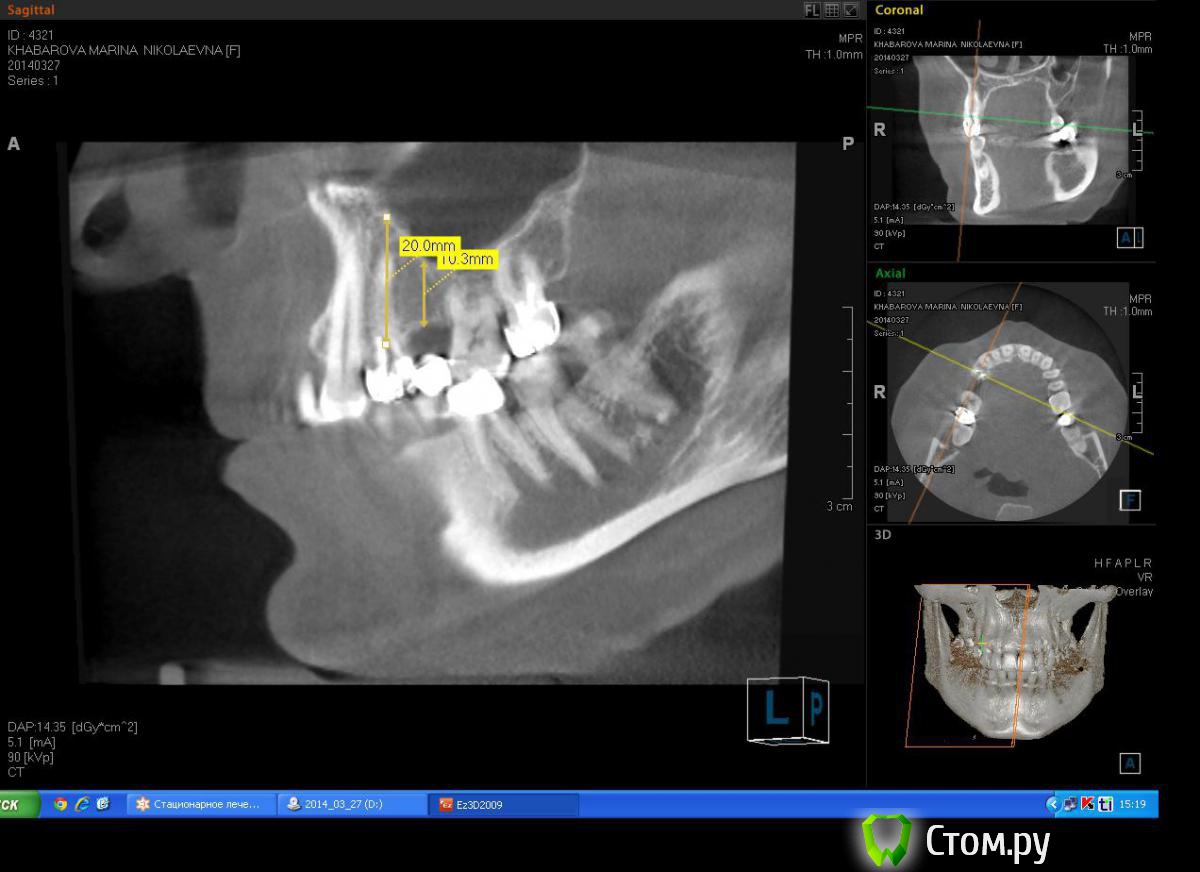

Milanomoda Опубликовано 22 апреля, 2014 Автор Поделиться Опубликовано 22 апреля, 2014 Имплантацию в районе 14 зуба планирую ставить в область язычного корня, только вот вопросик такой, при одномоментном протоколе на сколько примерно заглублять нужно будет имплант? Ссылка на комментарий

Milanomoda Опубликовано 22 апреля, 2014 Автор Поделиться Опубликовано 22 апреля, 2014 Альфа био , SPI. В область 15 планирую 4.2х8 , в область 14 - 4.2 на 13 либо 16 mm, пока что еще думаю...Костный материал - Bioss Ссылка на комментарий

Milanomoda Опубликовано 22 апреля, 2014 Автор Поделиться Опубликовано 22 апреля, 2014 Картина с планируемым 4.2 х 16 мм имплантом в области 14. Ссылка на комментарий

DShu Опубликовано 22 апреля, 2014 Поделиться Опубликовано 22 апреля, 2014 4,2 думаю им там тесновато будет. 4,5 тем более.На 14 я бы поставил 3,75*16 (или на 13) на 15 - 3,75*10 бикортикально. Сразу формики, вокруг - графт или без него, кто как любит) 3 Ссылка на комментарий